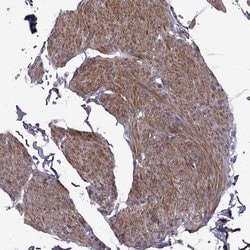

| Immunohistochemistry (Paraffin), Immunocytochemistry | |